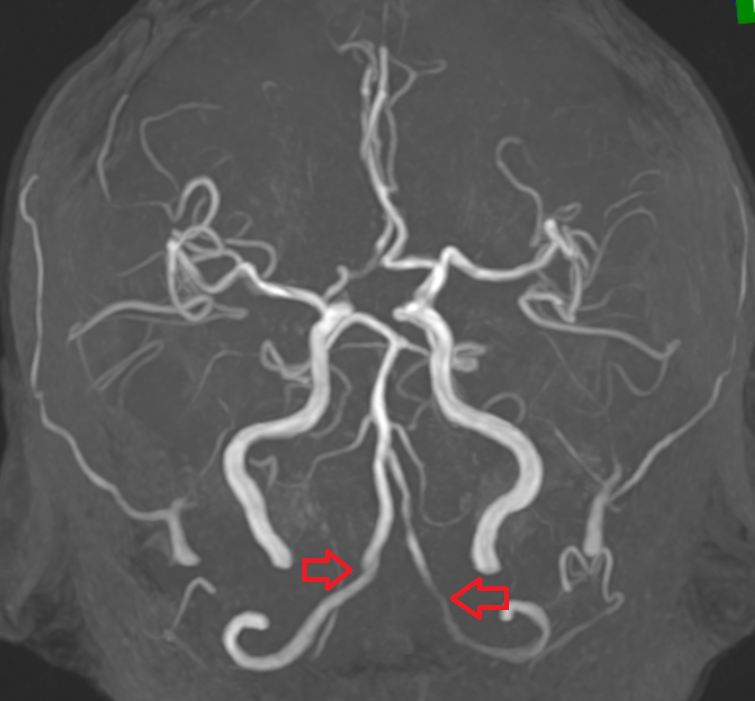

왼쪽 윗배(좌상복부)에는 비장(지라), 췌장(일부), 위, 신장, 좌측 폐 하부, 대장(비장만곡) 등 여러 장기가 밀집해 있어 정확한 진단 없이는 원인을 쉽게 알기 어렵고, 치료 시기를 놓치면 내출혈, 췌장염 악화, 장기 파열 같은 심각한 상황으로 번질 수 있습니다.